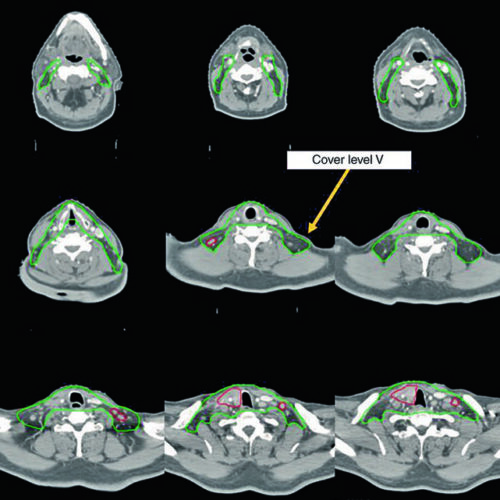

Delineamento de volumes-alvo e OAR em tumores de cabeça e pescoço: nasofaringe, orofaringe, laringe, hipofaringe, cavidade oral, seios paranasais, glândulas salivares e tireoide.